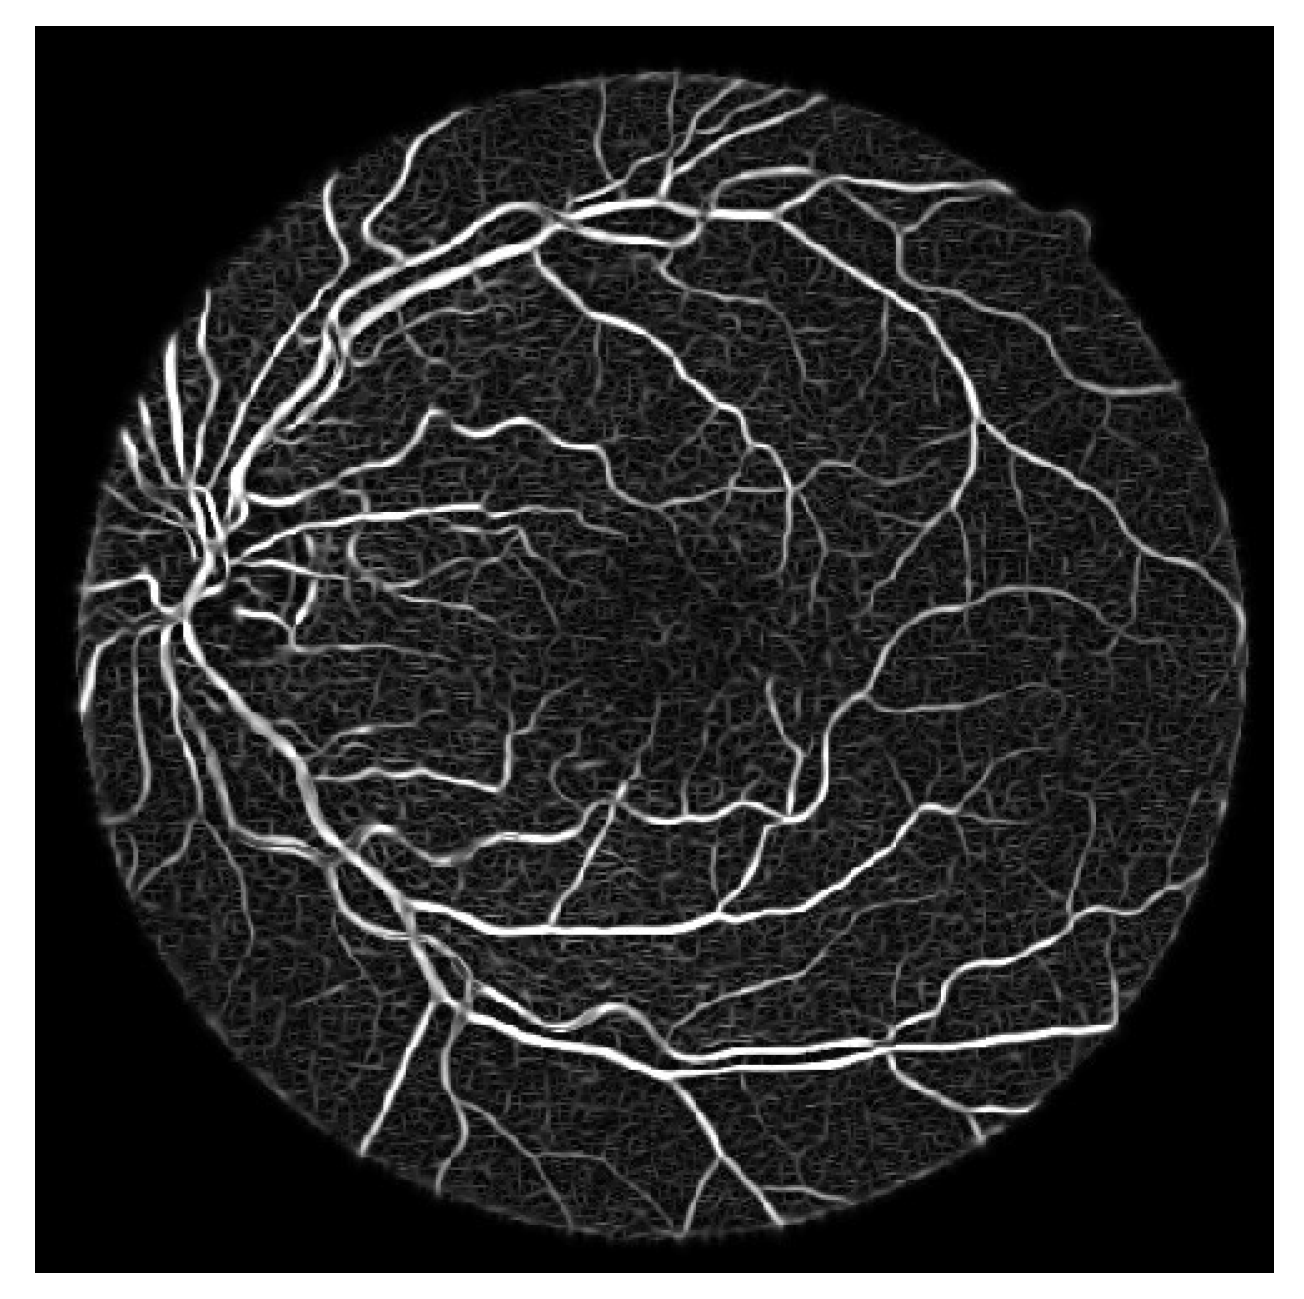

- Process the updated image based on the difference formula depicted equation below and achieved coherent vessels image as shown in Figure 11